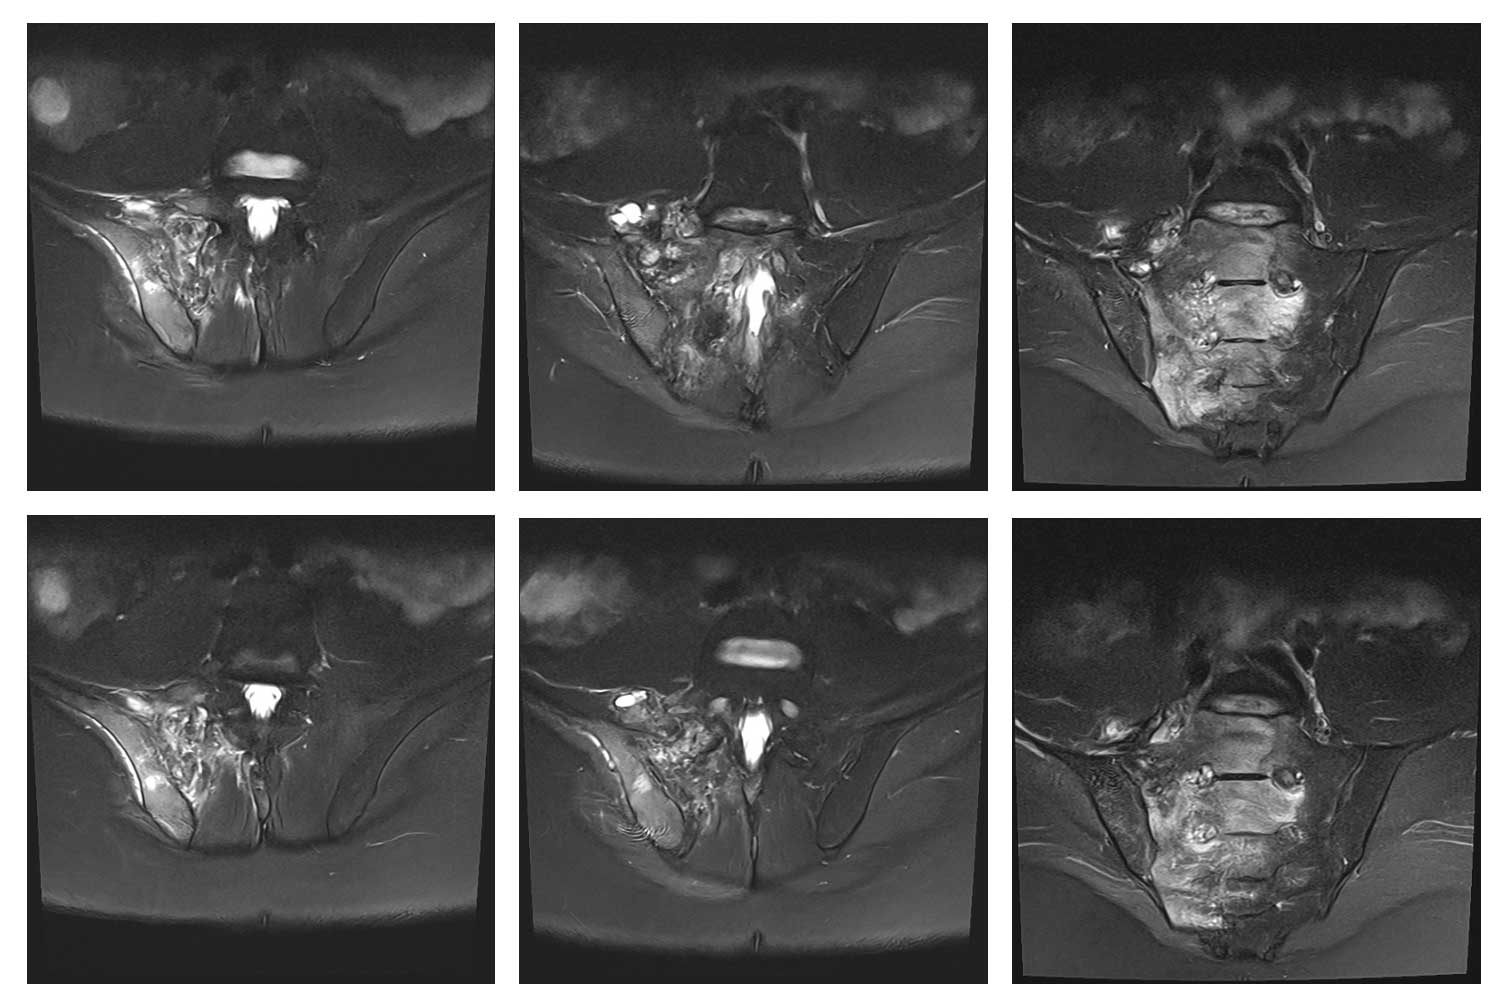

Ameliyat Öncesi: MR’da sağ iliak kanat posterior sakroiliak bölge üst kısım ve sakrumun tamamına yakınını kapsayan tümör dokusu ve çevreleyen ödem görülmekte.